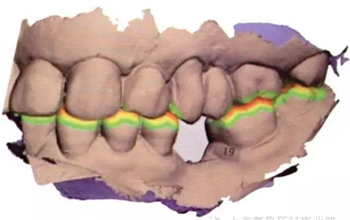

在此次就診中,也用TRIOS掃描儀(3Shape;圖2與圖3b-d)掃描左側(cè)上下頜骨和上下牙弓并進(jìn)行咬合重建。只要把所有的診斷信息收集起來(lái),第二天就可以復(fù)診治療。

將從CBCT中獲得的數(shù)字掃描文件和DICOM文件導(dǎo)入到Implant Studio軟件中(3Shape),一種新的空間技術(shù)可以創(chuàng)建口腔內(nèi)真實(shí)情況的三維重疊圖像和放射圖片。Implant Studio中的修復(fù)性設(shè)計(jì)工具可用來(lái)在修復(fù)表面圖片上創(chuàng)建一個(gè)處于理想修復(fù)位置的符合功能性和美觀性的虛擬牙冠(圖4a-d)。